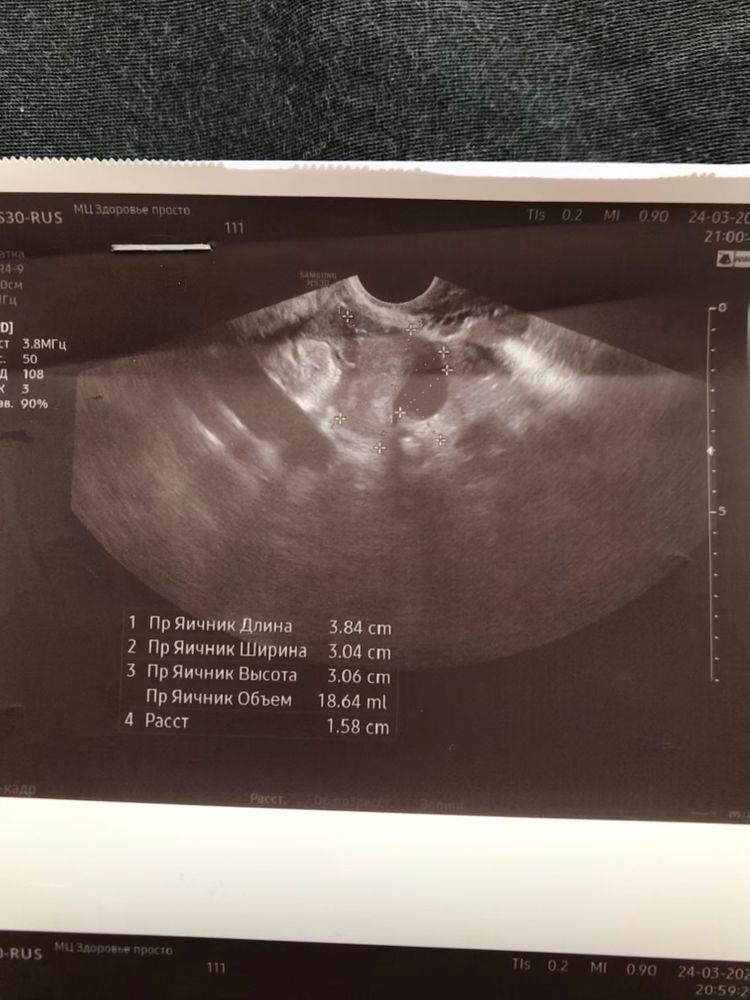

Двойня? УЗИ

в правом 18 мм

в левом 23 мм

Дарья , то что вы пишете 18 и 23 это обьем яичника, а не желтые тела же, честно говоря, по этим фотографиям мне непонятно, где желтое, просто размеры.

ЗеленоглАзая, это размер желтых тел. На фото написано

Дарья , прочитайте внимательнее, это обьем) он складывается из трех измерений яичника, которые сделаны выше и автоматически рассчитывается аппаратом.